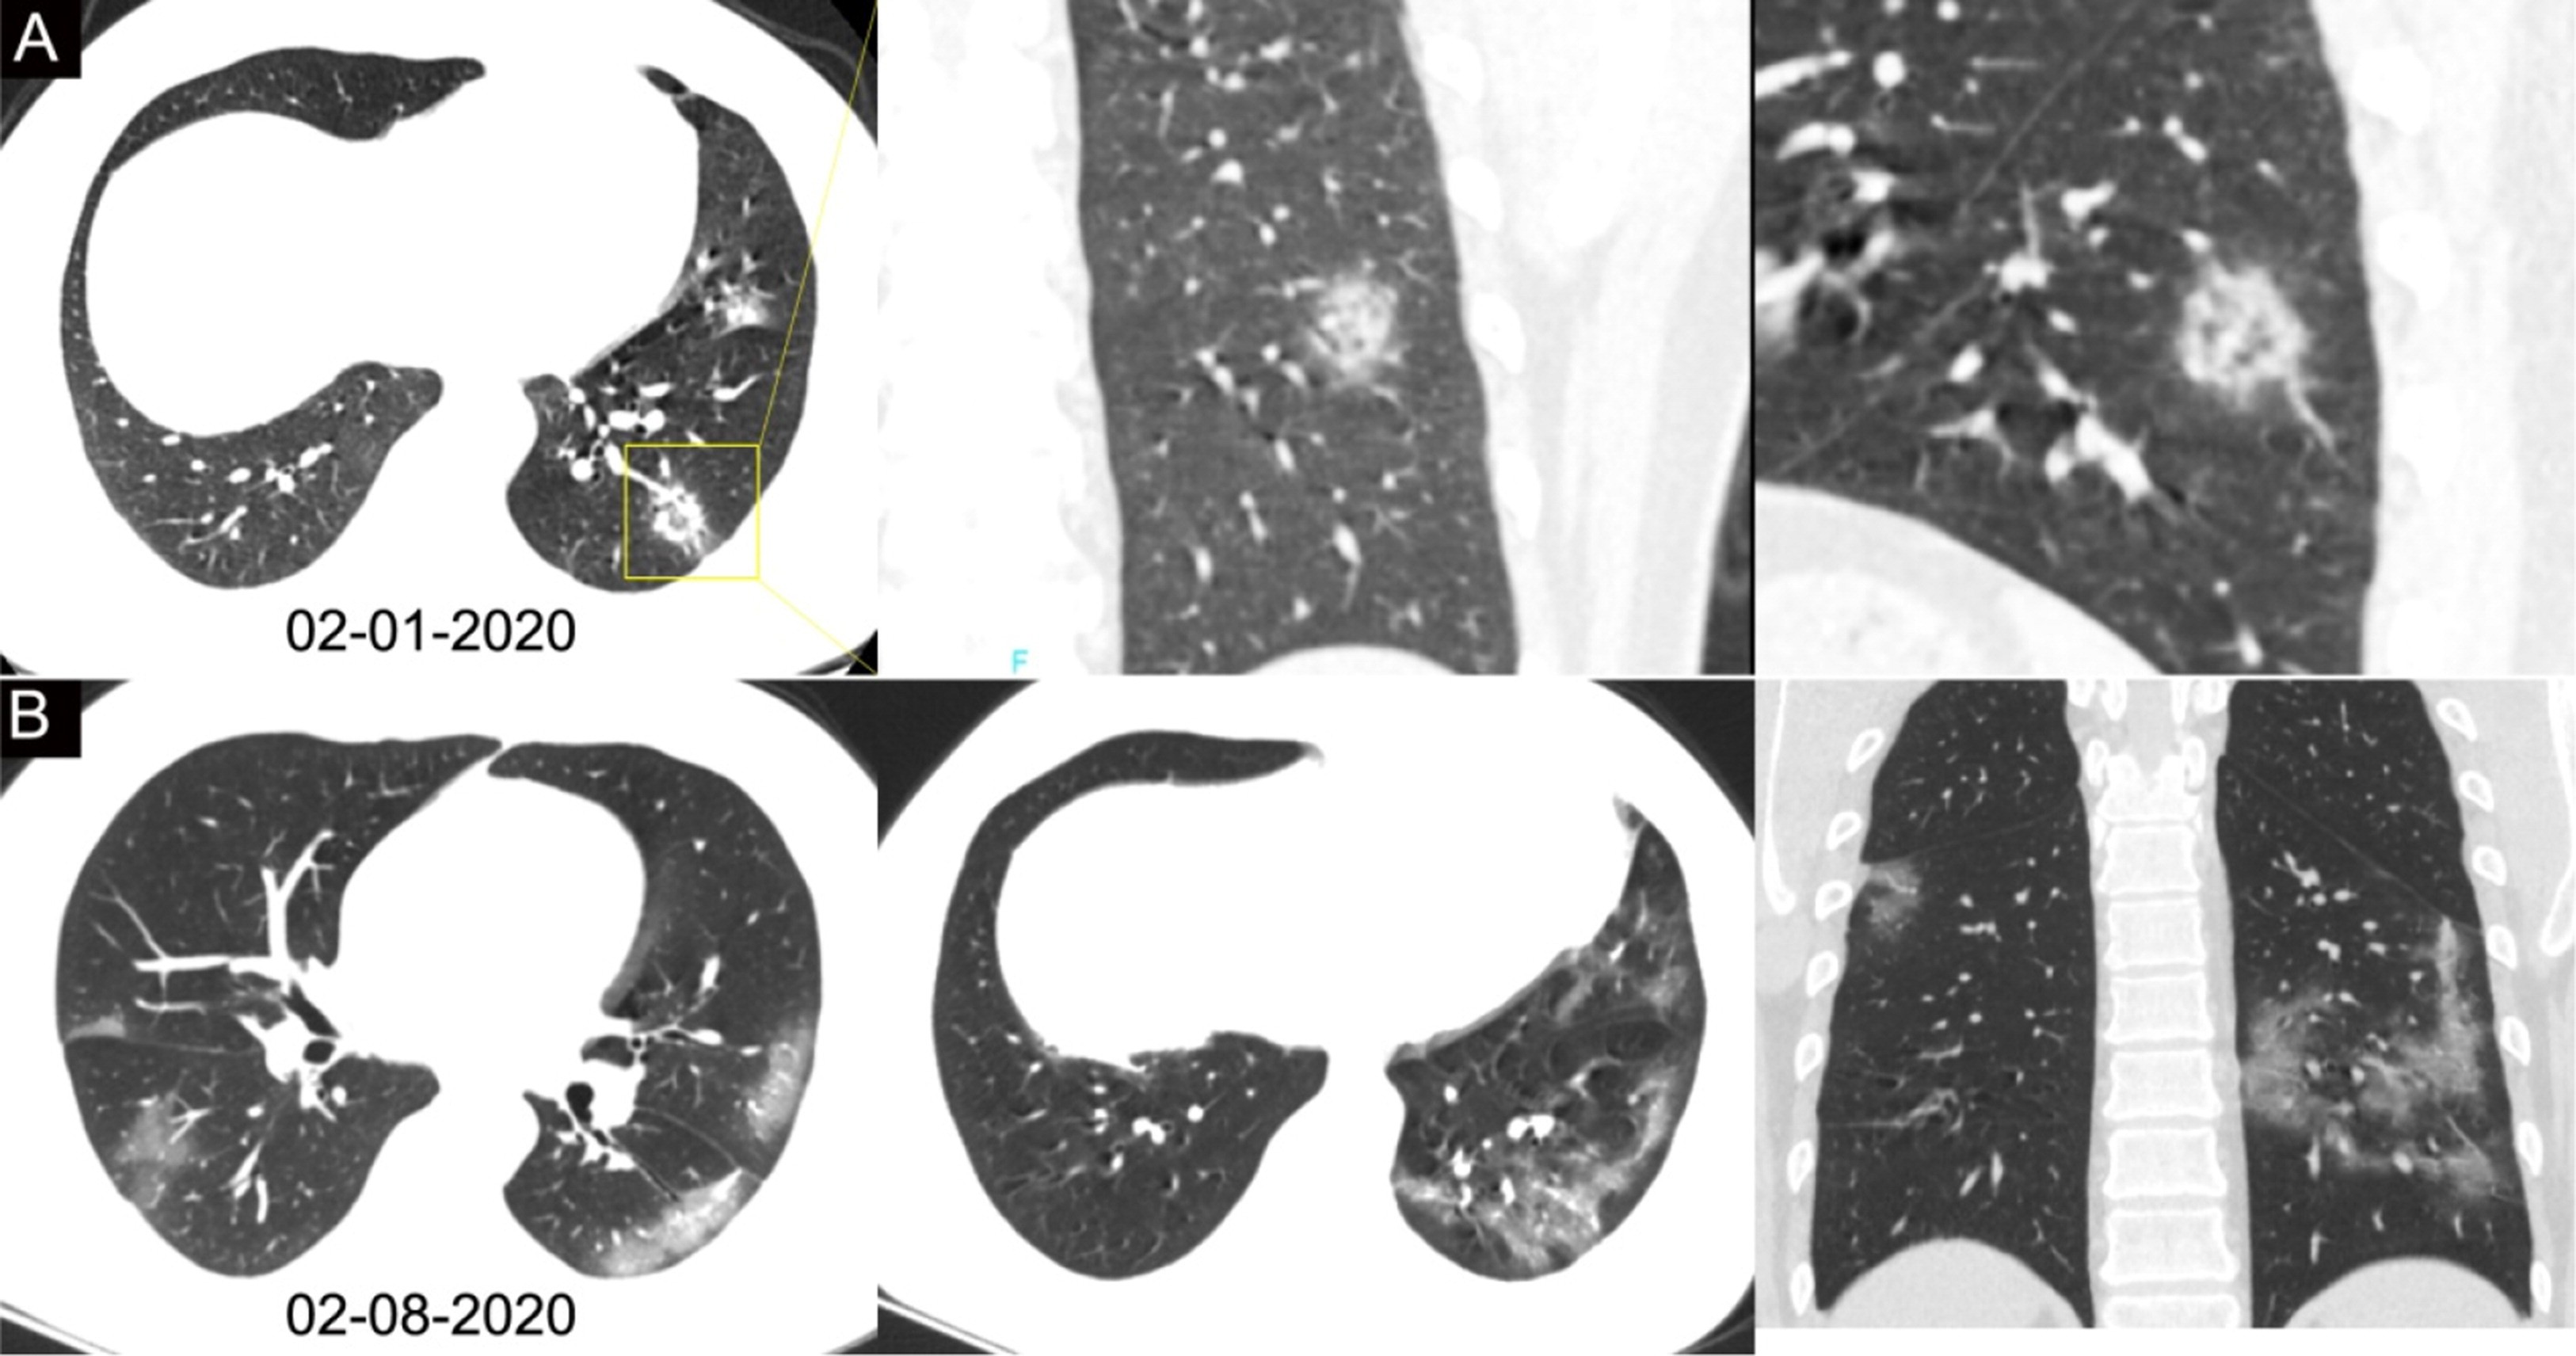

Пневмонии sars

Пневмонии sars 113 фото